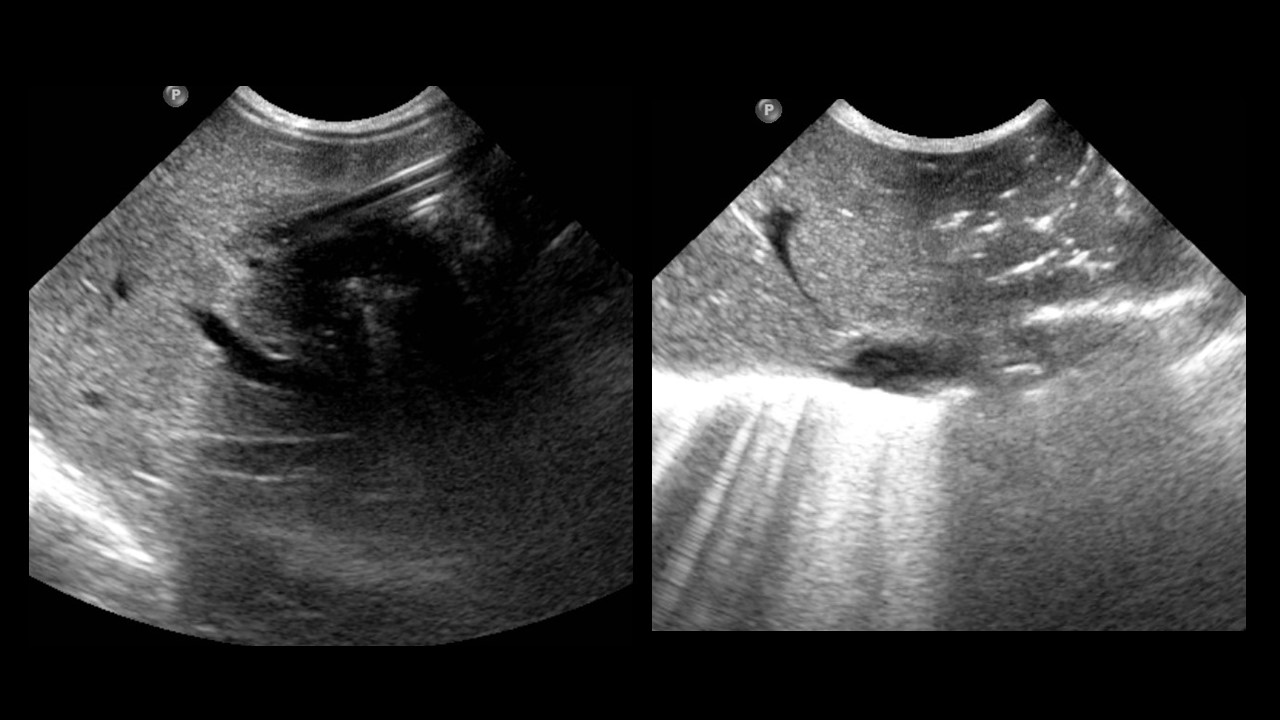

Prematuro de 34 semanas al que se le ha realizado la siguiente exploración.

¿Cuál de las siguientes afirmaciones es correcta:?

Se observa una consolidación en el lóbulo inferior derecho con broncograma aéreo.

Se observa dilatación patológica de las asas intestinales.

La vía se encuentra mal colocada.

El radio izquierdo se encuentra luxado.

La radiografía es normal.